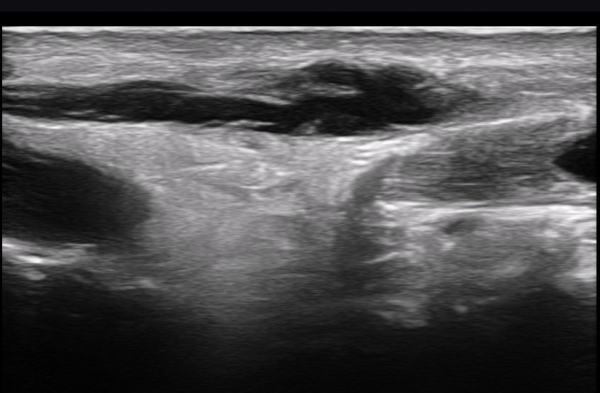

ºñº¹½Å°æ Á¾´Ü¸é°Ë»ç(»çÁø 14, 15)¿¡¼­ ºñº¹½Å°æÀÇ Àü¹ÝÀûÀÎ Àú¿¡ÄÚ ºÎÁ¾°ú ºñº¹½Å°æ ½ÉÃþÀ¸·Î ´Üºñ°ñ°Ç³»

³¶Á¾¼º º¯º¯ÀÌ °üÂûµÈ´Ù.